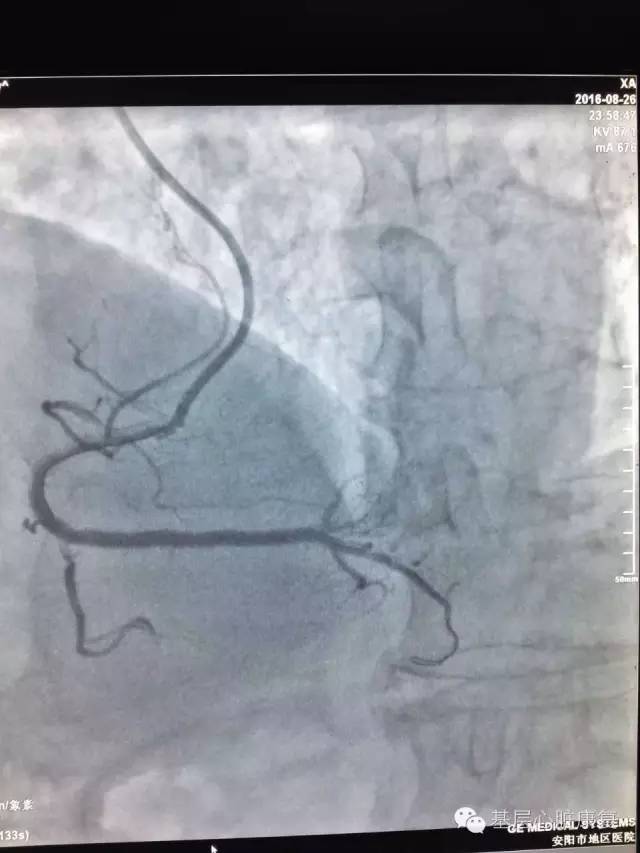

胜利喜悦

这时看一下墙壁上的钟表,已是深夜12:00了,不知不觉手术已进行了3个半小时。夜已深,大家已进入甜蜜的梦乡,而他们却为手术挑战的成功感到振奋,为患者感到由衷的高兴。他们渴望每一个患者的痊愈,渴望每一次手术的成功,渴望迎接每一次的挑战,他们一直在不懈的努力着……